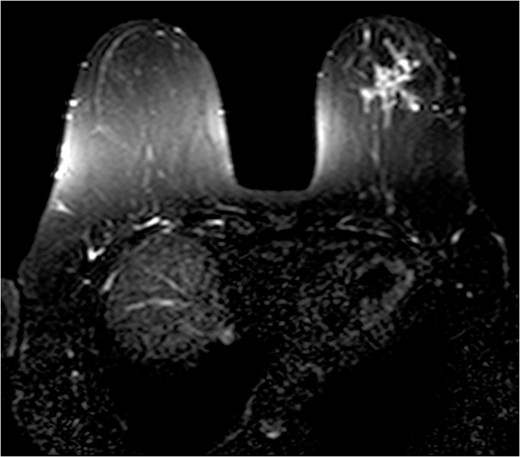

The patient was then sent for MRI of the breast to detail the extent of the remaining mass. This revealed an ill-defined mixed linear and fine nodular enhancing tumor 6.5 × 4.6 × 4.8 cm in size with BI-RADS 5 (Figs 4–7).

The role of MRI in identifying the extent of breast carcinoma is widely reviewed. EPC has been noted to have multifocal hyperintensities at T1 weighted imaging. Contrast MRI will reveal enhancement of the cystic wall, septa and mural nodules [4].